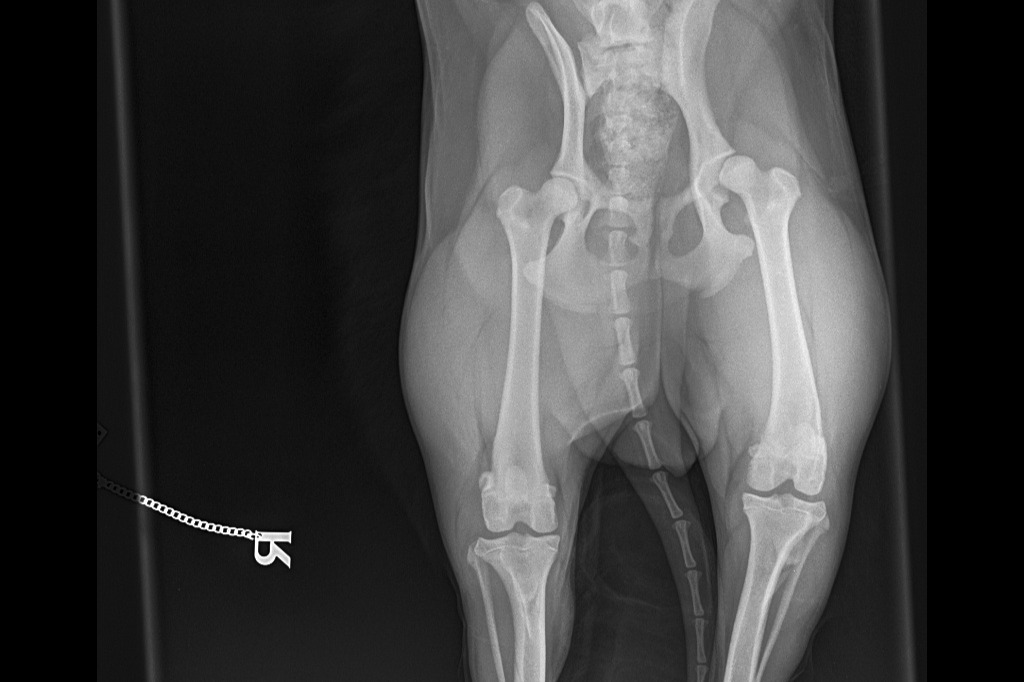

I can't walk anymore and the Vets said I have Luxating Patella issues and I need a surgery. I am scared to wee/poo because my legs would hurt if I flex/squat to wee/poo. My pictures below are the recent pictures after this incident and before the incident. If you want to see more pictures of me being lively and happy, please check my Instagram Profile lupe_gordita.